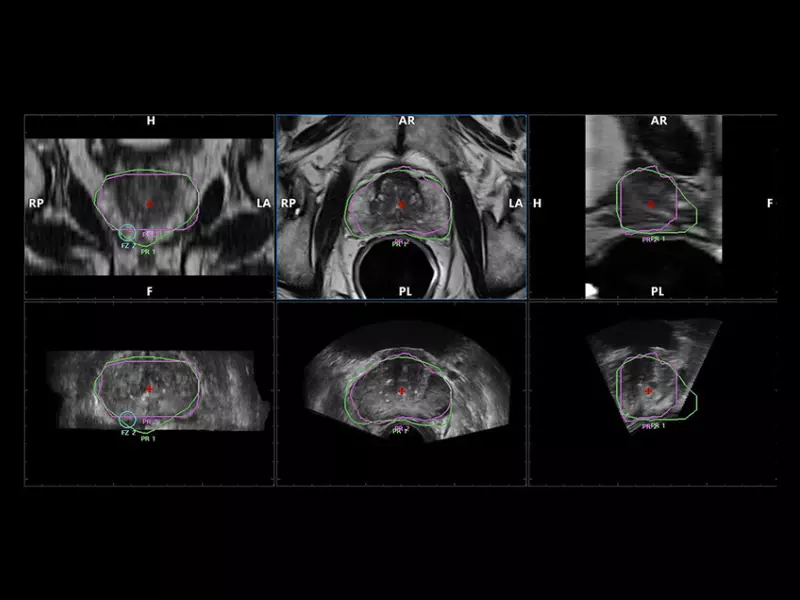

MyLab™X90 - UroFusion Automatic segmentation of the prostate MRI/US, followed by autoregistration of both modalities for targeted biopsies

MyLab™X90 - UroFusion Automatic segmentation of the prostate MRI/US, followed by autoregistration of both modalities for targeted biopsies

MyLab™X8 Platform - Prostate biopsy with Virtual Navigator fusion imaging 3D

MyLab™X8 Platform - Prostate biopsy with Virtual Navigator fusion imaging 3D

MyLab™E80 - Urofusion - TP Biopsy

MyLab™E80 - Urofusion - TP Biopsy

MyLab™E80 - Urofusion - Systematic Biopsy Guide

MyLab™E80 - Urofusion - Systematic Biopsy Guide